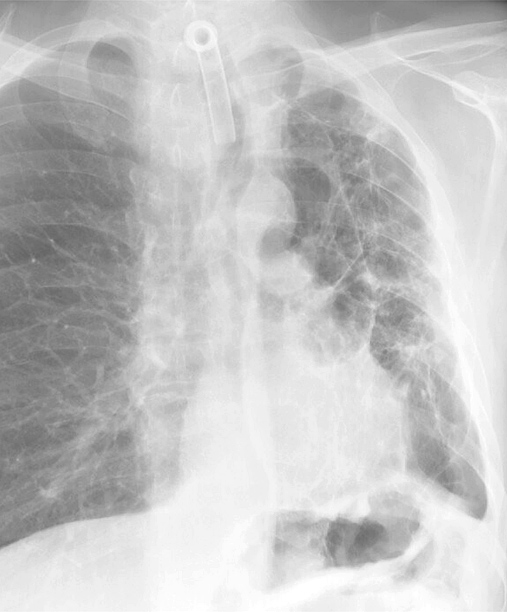

Gallery Pulmonary Fibrosis IPF Case 2a

Case 2a